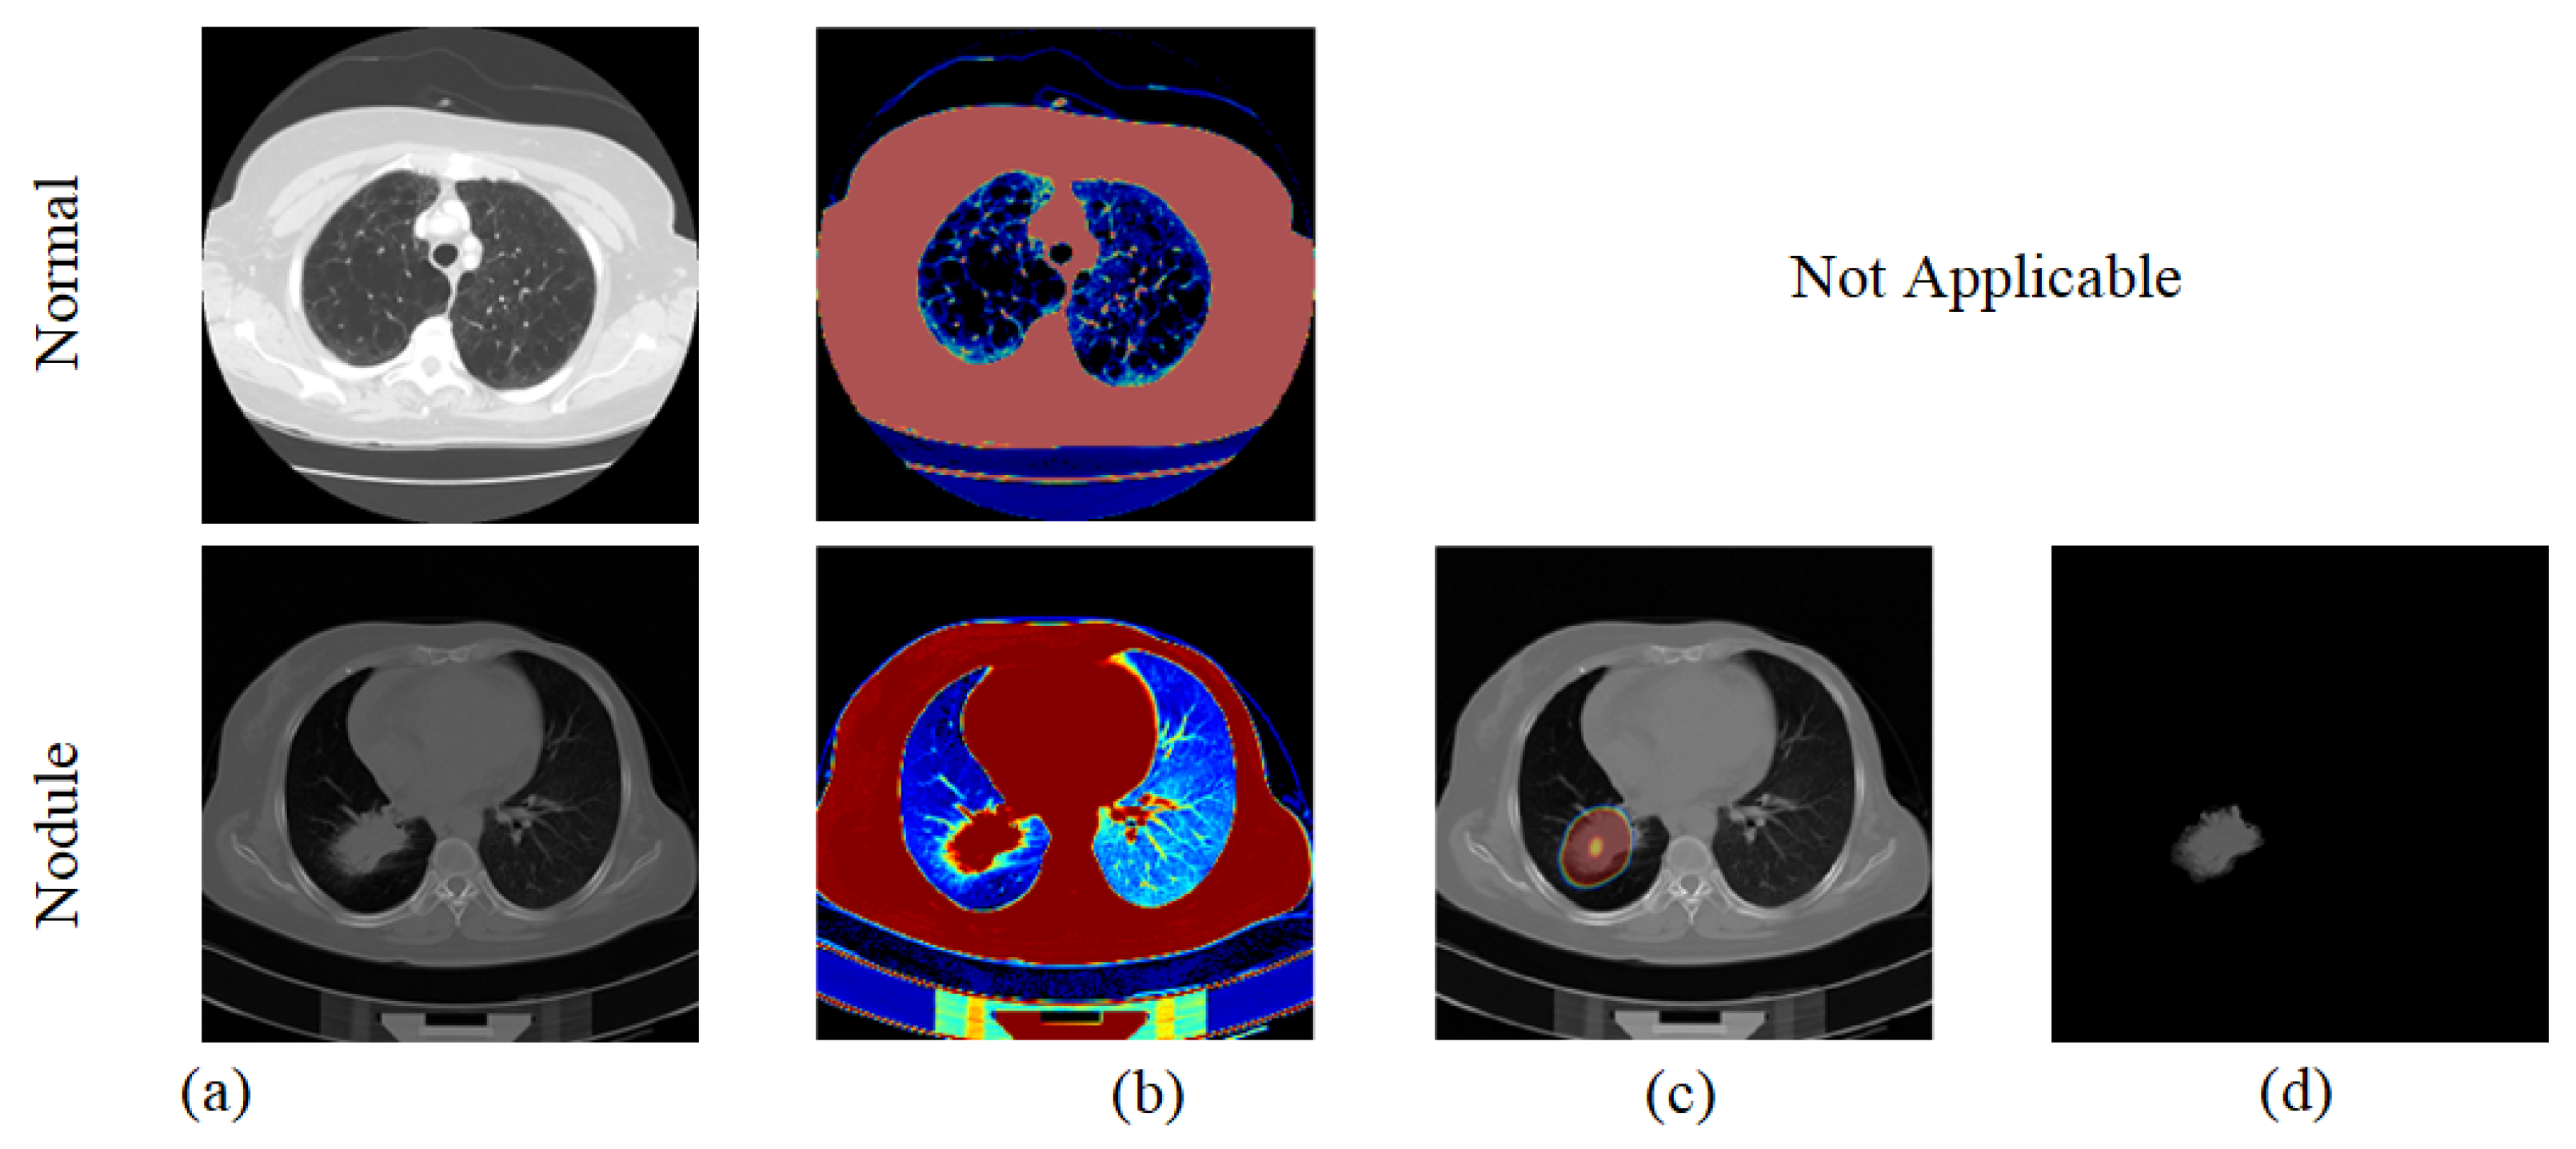

3.2. Nodule Segmentation